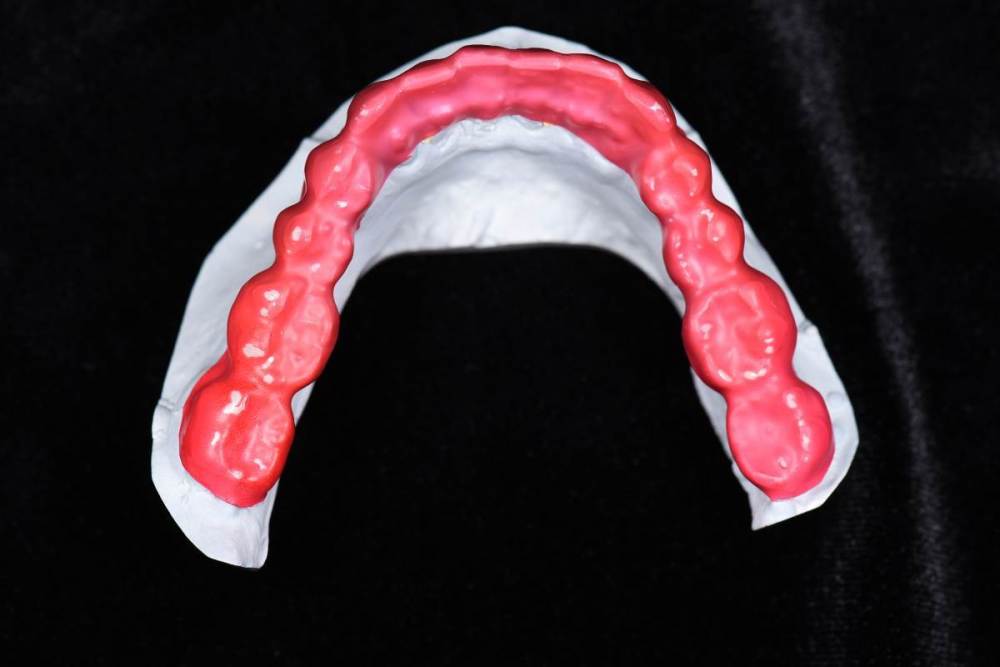

Брукс чекеры:

DSC_0402.thumb.JPG.9053cba49785bf22984aecb4de6cbc02.JPGDSC_0403.thumb.JPG.2015cfab9c333c8bf57e8b673ced91ac.JPG

Закончил тотал и решил поделиться. Протезировали с учетом положения ВНЧС в концепции Славичека.  В конце изготовление брукс чекеров для проверки нежелательных контактов во время сна.  Гигиену пытаемся победить...